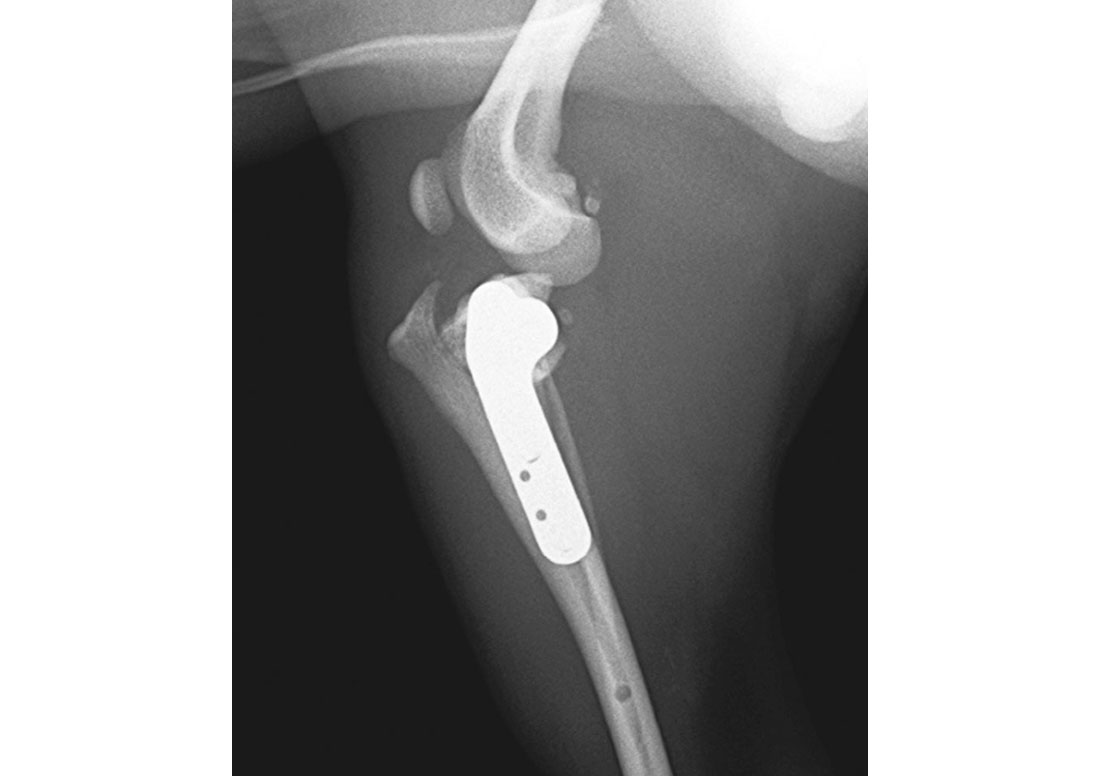

特に専門性の高い手術

前十字靱帯断裂に対する

TPLO手術

前十字靱帯断裂は、犬に多くみられる膝関節疾患で、適切な手術と術後管理が、歩行機能の回復に大きく影響します。

当院では、前十字靱帯断裂に対する治療として、TPLO(脛骨高平部水平化骨切り術)を数多く実施してきました。

関節鏡は使用していませんが、直接視野下で関節内の状態を丁寧に確認し、症例ごとに必要な処置を確実に行うことを重視しています。

使用するインプラントは、シンセス社・VOI社・FIXN社の製品を採用し、それぞれの症例の脛骨形状や体格に応じて適切なものを選択しています。

特に小型犬の症例にも多く対応しており、安定性と安全性を重視した手術を行っています。

これまでに積み重ねてきた豊富な症例経験をもとに、術後の生活まで見据えたTPLO手術を提供しています。